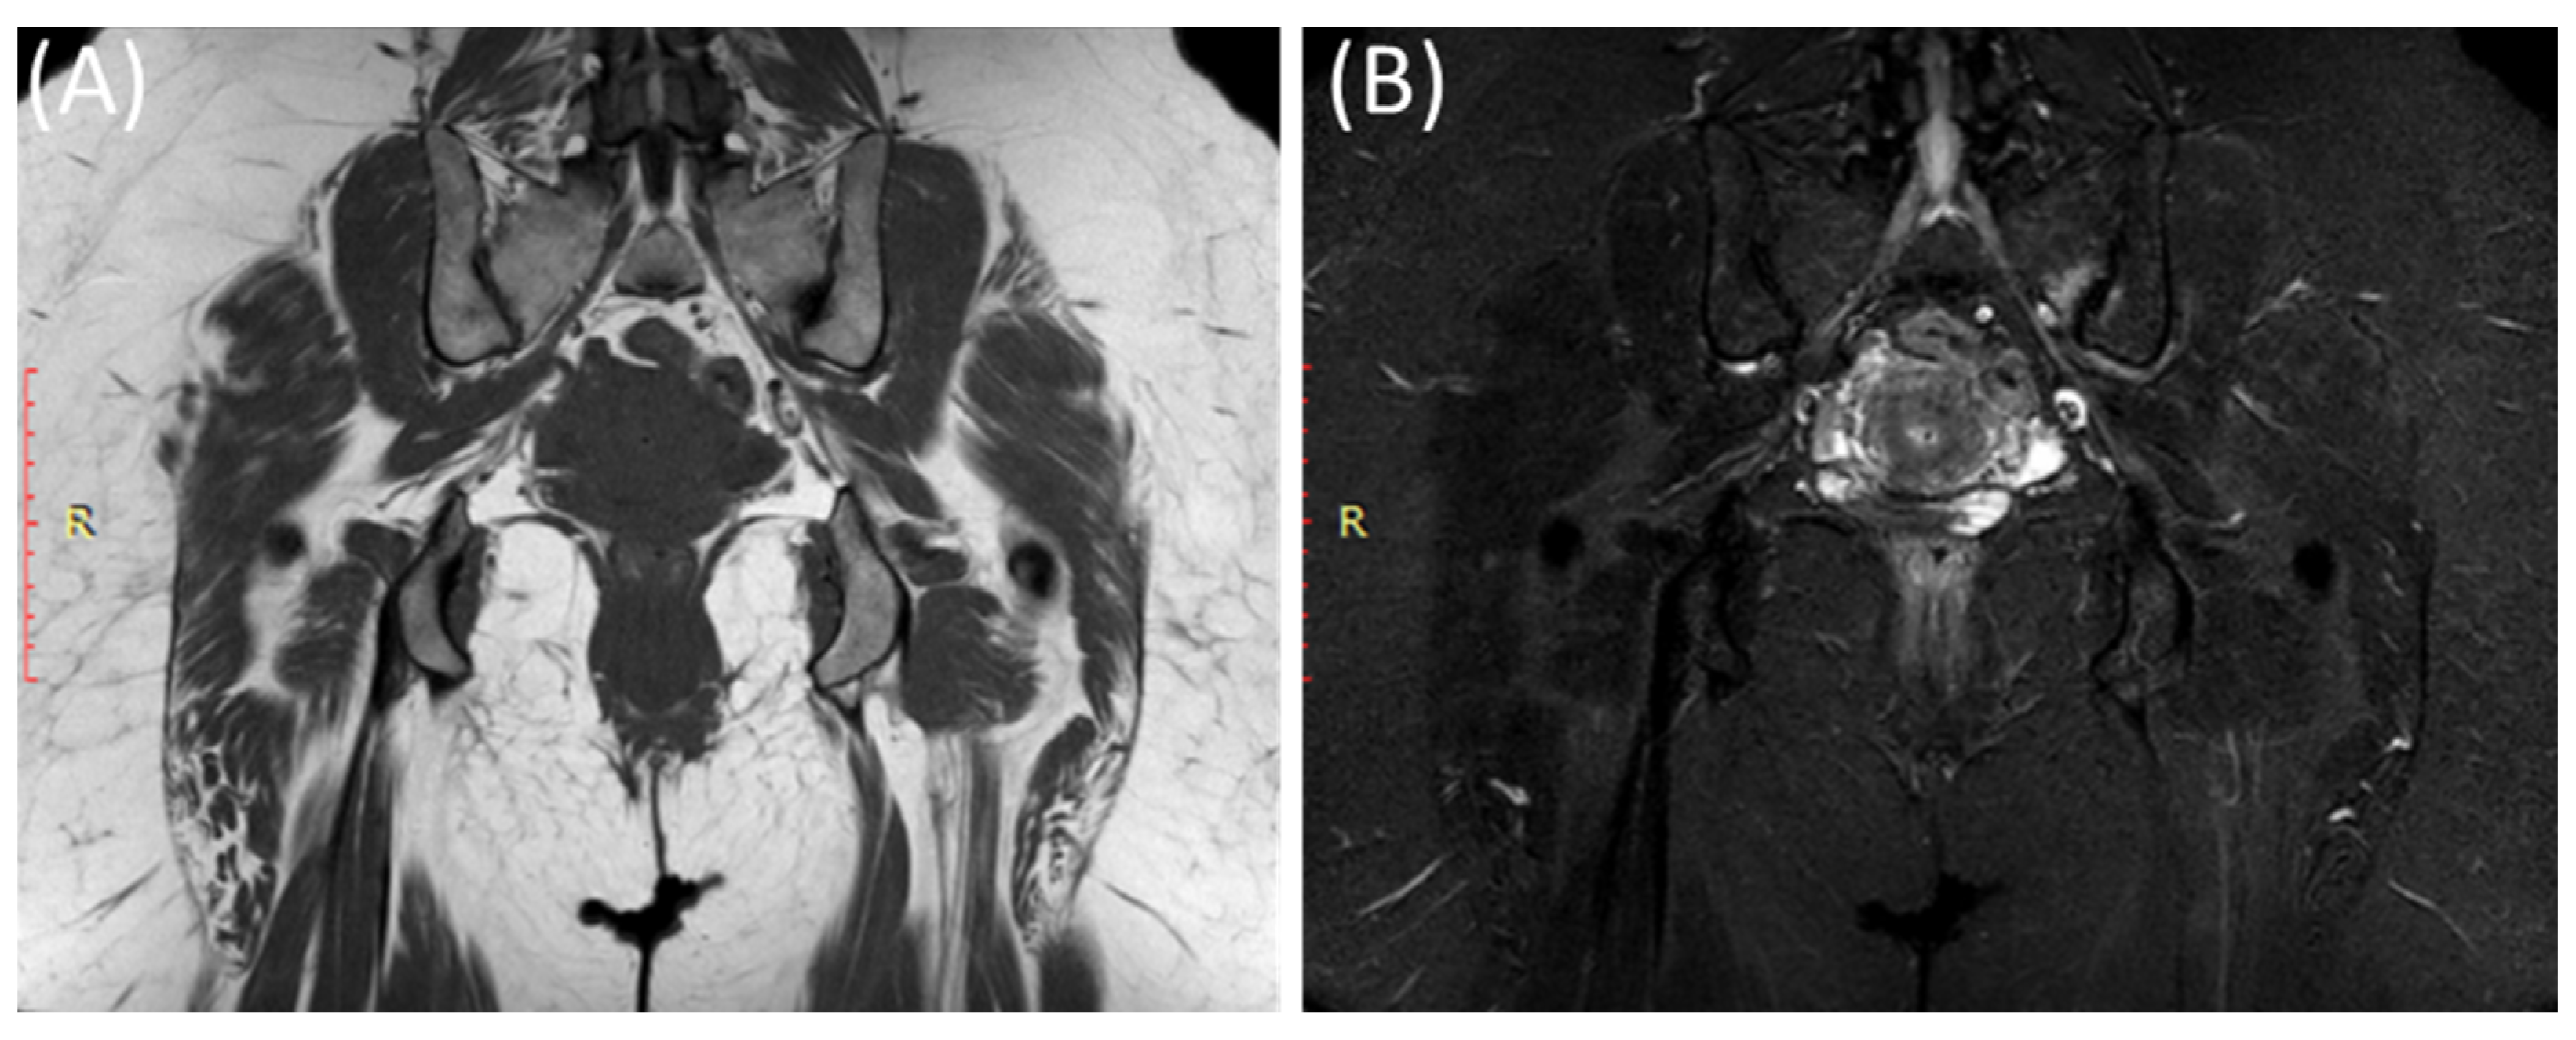

Figure 7.

Coronal T1WI image (A) and STIR image (B) showing edema and irregularity in the left sacroiliac joint in a 47-year-old female with lower back pain and left sciatica with acute (active) sacroiliitis.